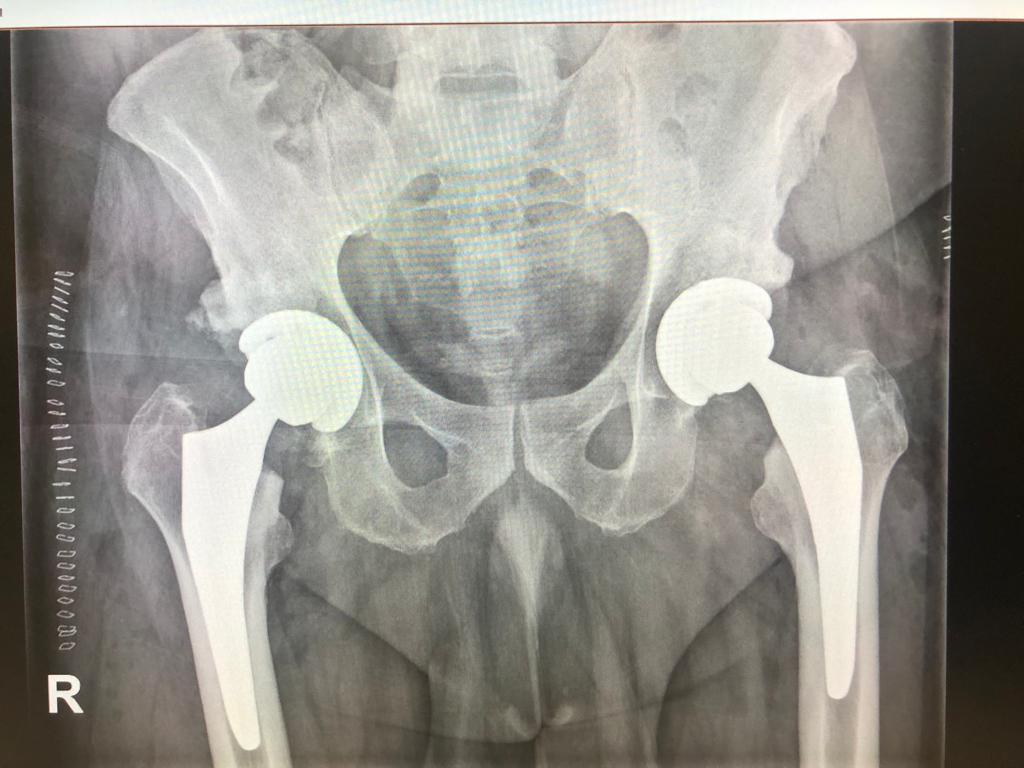

La última oportunidad ha recaído en el Doctor Jorge Guadilla, uno de los especialistas de nuestra Unidad de Cadera, quien se ha desplazado hasta el Hospital del Vendrell de Tarragona para participar en una intervención de cadera pionera por lo inusual de la misma.

En esta colaboración, el Doctor Guadilla ha tomado parte en una compleja cirugía para incorporar en el paciente una prótesis de cadera bilateral y simultánea a través de un abordaje anterior directo. Lo sustancial en esta ocasión es que al paciente se le ha operado a la vez de las dos prótesis de cadera al presentar una artrosis muy simétrica y limitante.

El resultado de la intervención ha colmado las expectativas de los cirujanos del propio Hospital del Vendrell, que junto al Dr. Guadilla confían en la pronta recuperación del paciente.